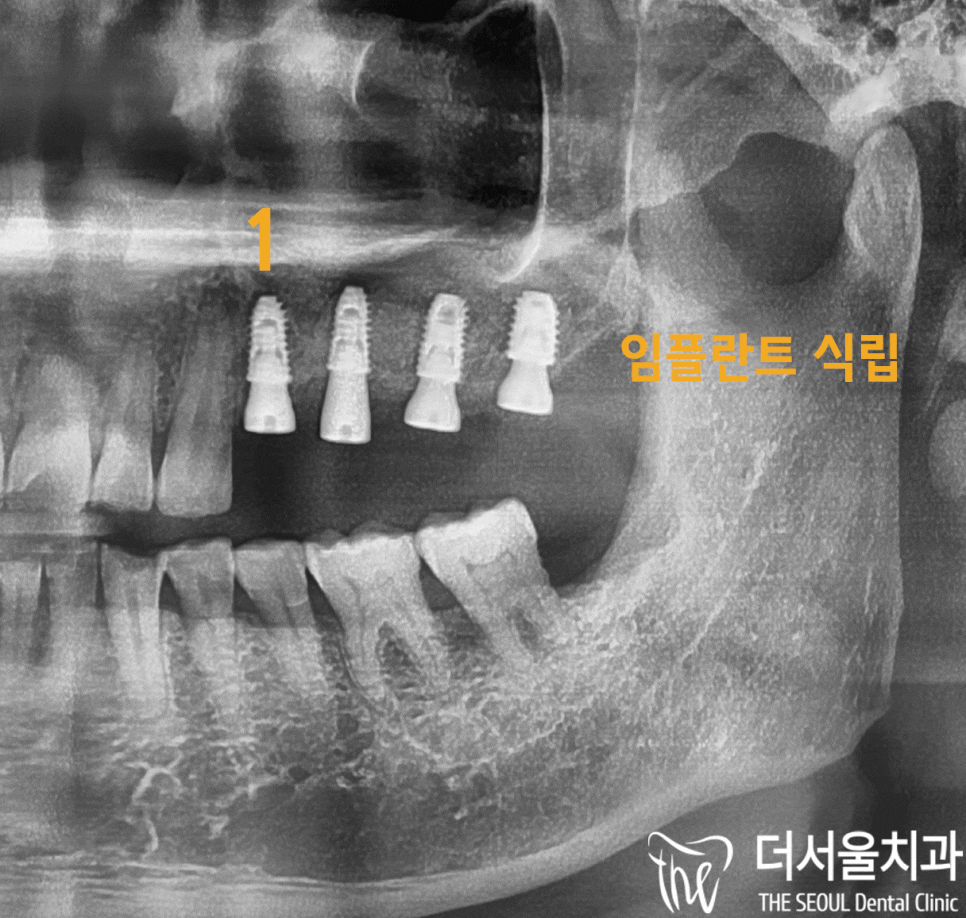

수술 전)

3D-CT 촬영을 통해서

모의 수술 을 진행하게 되었습니다.

사진에서 보는 것처럼

현재 남아있는 골질을 확인한 다음

임플란트 가 심겨질 위치를 파악하게 되었습니다.

이를 토대로

상악동 거상술 후 뼈이식재를 채워 넣고

어금니 부위에 임플란트 를 심을 수 있었습니다.

수술 후 모습을 보여드리겠습니다.

사진을 보면

총 4개의 임플란트 를 식립하고

뼈이식까지 완벽하게 해낼 수 있었습니다.

⭐여기서 중요한 건⭐

잇몸 절개 없이 진행했다는 점입니다.

출혈과 통증이

현저히 감소할 뿐만 아니라

치료 기간을 줄일 수 있다는 이점이 있습니다.